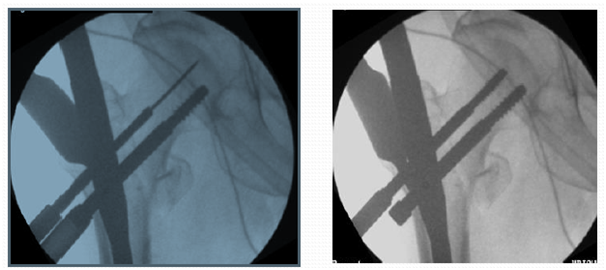

Entry point to be at tip with medial bias

In AP view entry point to be more medial. This allows 2 screws in head in good position (Figures 11&12).3

Figure 11 Entry point to be at tip with medial bias.

If too lateral entry point

If starting point is placed lateral to the tip of the trochanter it may result in varus malreduction (Figure 13).4-7

Figure 13 Lateral entry point, pushed proximal fragment into varus and screws into malposition.